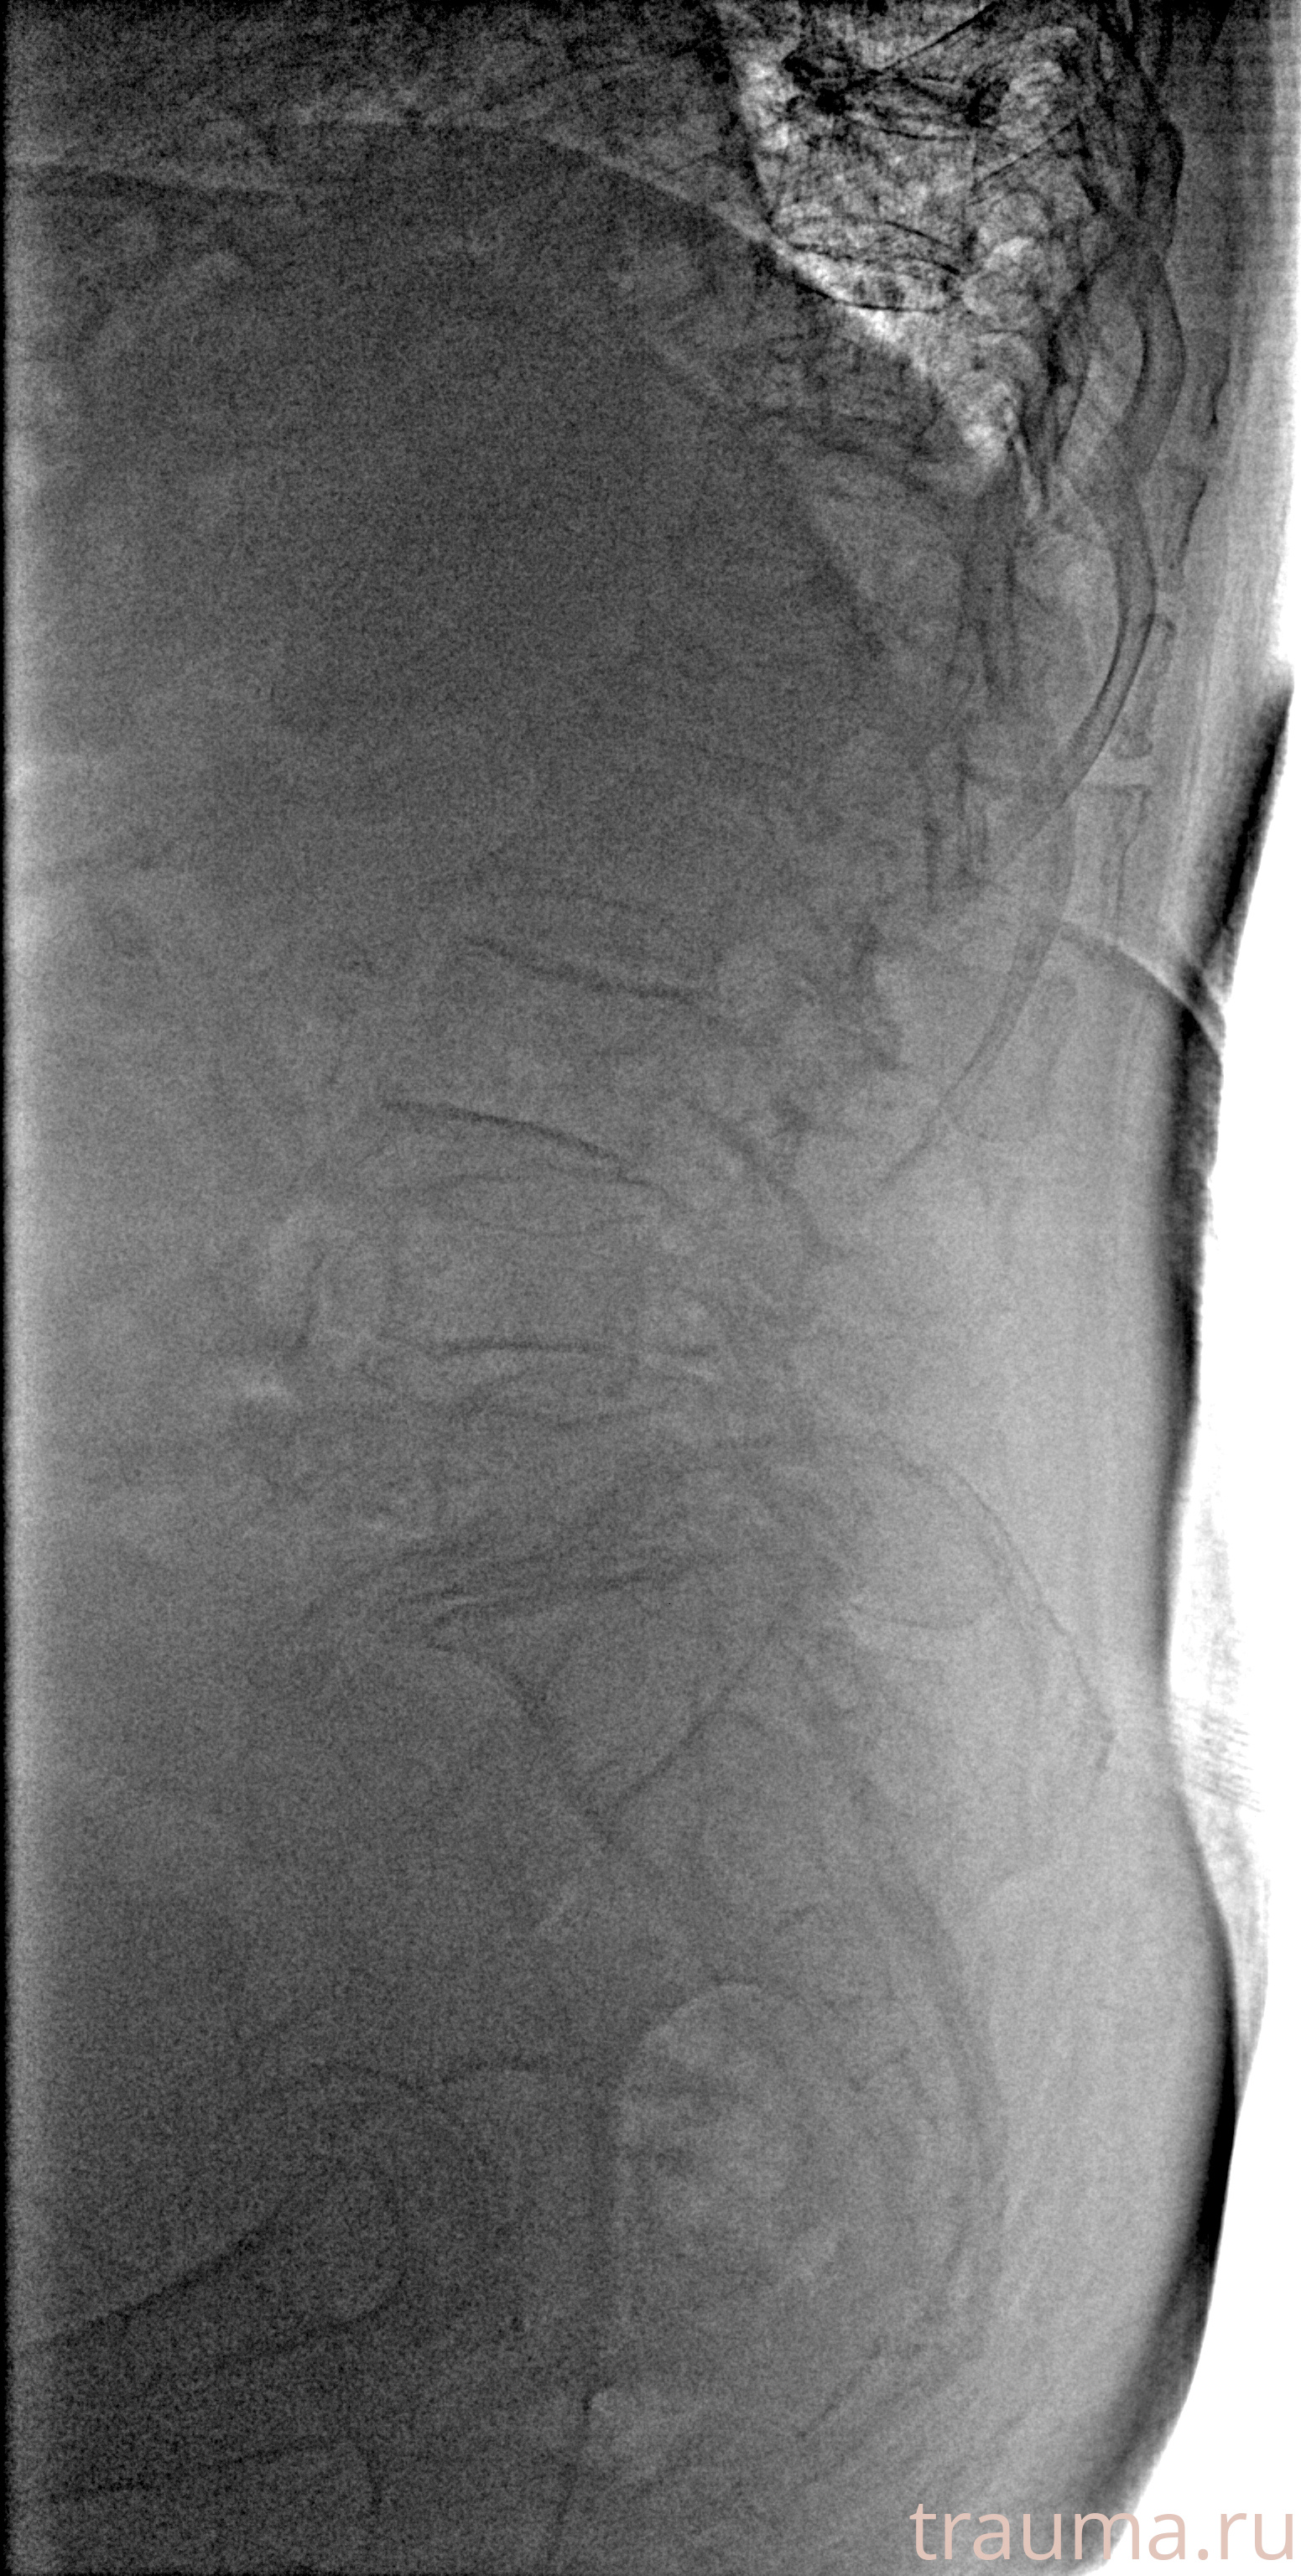

Рентгенограммы

Рентген на дому: по вашему адресу приезжает врач-рентгенолог, травматолог-ортопед с мобильным рентгеновским аппаратом, проводит диагностику травмы или заболевания, делает необходимые рентгенограммы, дает рекомендации по дальнейшему лечению. Получить качественные снимки в домашних условиях возможно благодаря уникальной методике, разработанной МосРентген Центром для института  Склифосовского